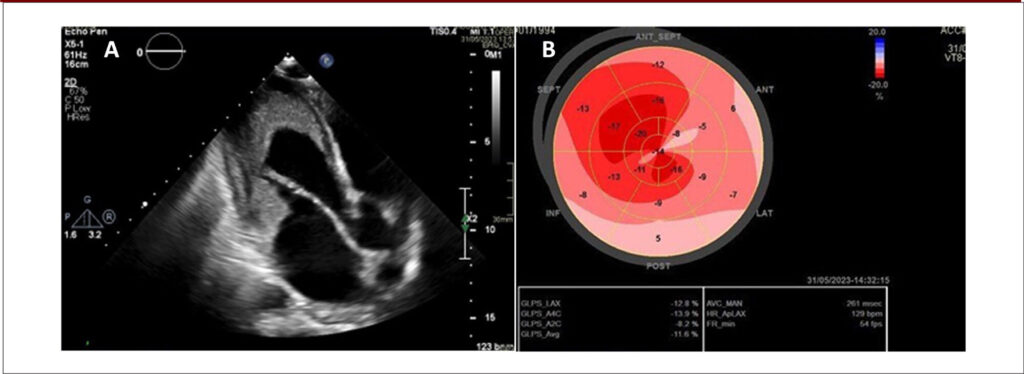

Important Mitral Regurgitation and Ventricular Dysfunction in Hypereosinophilic Syndrome: A Case Report

This article describes a case of eosinophilic endomyocardial disease, also known as Loeffler syndrome, a manifestation of HES characterized by eosinophil-mediated cardiac damage. Despite adequate treatment and control of the hematologic disease, the patient developed biventricular systolic dysfunction and important mitral regurgitation (MR).